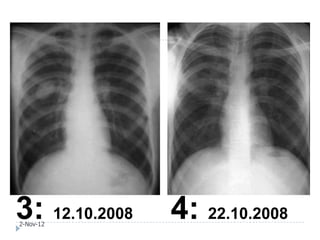

1: 15.09.2008 2: 20.09.2008

2-Nov-12

3: 12.10.2008

4: 22.10.2008